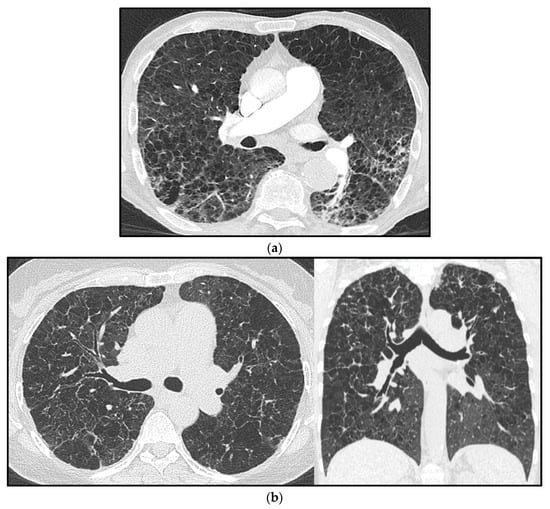

From a practical point of view, to suspect the development of PH associated with chronic hypoxia, parenchymal abnormalities on HRCT should be evident (even in the absence of a validated threshold of disease extent) (Figure 6a), associated with reduced FEV1 (˂60% of the predicted value) and DLCO, consistent with obstructive/restrictive changes [36].

Figure 6.

Pulmonary hypertension (PH) in a chronic obstructive pulmonary disease (COPD) patient with confluent centrilobular pulmonary emphysema (a). Multiple confluent bilateral irregular cysts in a patient affected by advanced pulmonary Langerhans’ cell histiocytosis (PLCH), complicated by PH (note the increased mean pulmonary artery diameter) (b); in advanced cases, the distribution of parenchymal abnormalities shows a rather diffuse longitudinal distribution, as seen in the coronal view, and the differential diagnosis with pulmonary emphysema is not straightforward.

In the appropriate clinical setting, radiologists can make a confident diagnosis of PLCH [95]. The pathological hallmark of PLCH is the accumulation of Langerhans’ cells and other inflammatory cells within the small airways, resulting in nodular inflammatory lesions. These nodules commonly cavitate and form cysts, representing enlarged airways. HRCT shows a predominantly nodular pattern in the early phases of the disease and a predominantly cystic pattern in the late phases; the cysts have been described as bizarre and usually spare the costophrenic recesses [95].

Advanced PLCH, when PH is usually more frequent, may have HRCT imaging features with large cysts and extensive lung parenchyma disruption, which overlap with emphysema and/or fibrosis as well as with LAM (Figure 6b). Therefore, in advanced cases, differential diagnosis among these entities may be challenging, and the typical radiological presentation of early PLCH (small nodules, sparing of posterior costophrenic recesses) make it difficult to recognize; it could be helpful to compare images with previous exams and to look for small cysts with bizarre morphology, peculiarly present in PLCH [18].